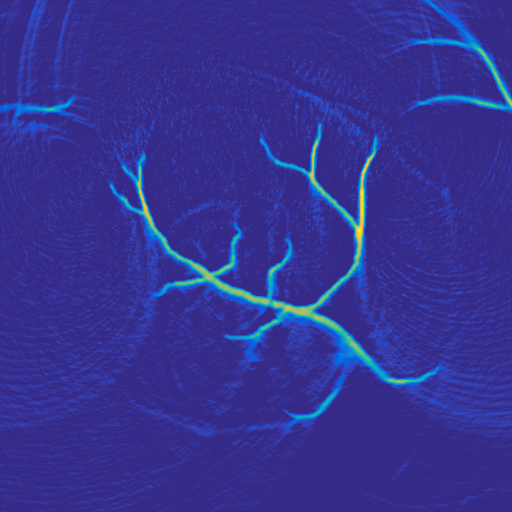

A 2D scenario: Ω=[0,1]2Ωsuperscript012\Omega=[0,1]^{2} with inhomogeneous medium properties and an irregular sensor geometry, see Figure 1. The medium properties vary in the range encountered, e.g., in the human breast [19].

Figure 1: 2D PAT scenario (II) used in the numerical studies. The spatial resolution is N=5122𝑁superscript5122N=512^{2} plus 242424 pixels of PML layer in all directions. LABEL:sub@subfig:2DScenarioA The scenario cosists of three materials: Material A (covering the top part of the domain): c=1500𝑐1500c=1500, ρ0=1000subscript𝜌01000\rho_{0}=1000, material B (parabolic-like part): c=1400𝑐1400c=1400, ρ0=1200subscript𝜌01200\rho_{0}=1200, material C (vessel-like part): c=1560𝑐1560c=1560, ρ0=800subscript𝜌0800\rho_{0}=800. LABEL:sub@subfig:2DScenarioB Ground truth p0subscript𝑝0p_{0} and sensor configuration (white pixels, 200200200 sensors at the interface between materials A and B.)